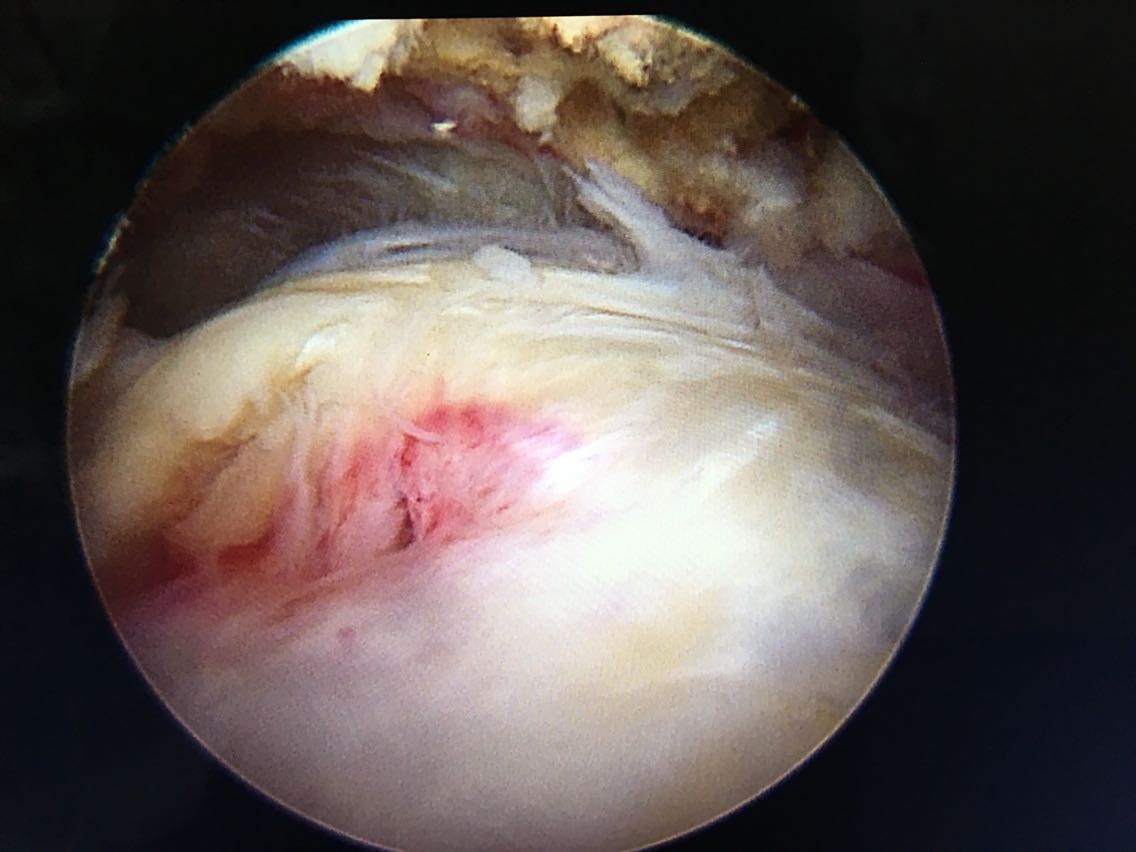

诊断:右肩袖撕裂 肩峰撞击症 冻结肩 治疗:关节镜下清理 肩峰撞击成形 肩袖撕裂修补手术。